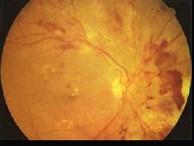

糖尿病眼部病变中导致失明的主要原因是()A.白内障B.微血管瘤C.硬性渗出D.视网膜小静脉扩张E.增殖性视网膜病变

问题 糖尿病眼部病变中导致失明的主要原因是()

选项 A.白内障 B.微血管瘤 C.硬性渗出 D.视网膜小静脉扩张 E.增殖性视网膜病变

答案 E